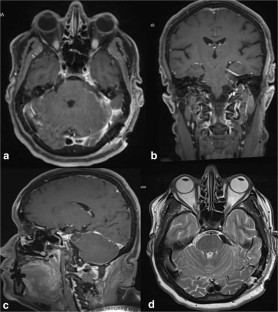

Fig. 1